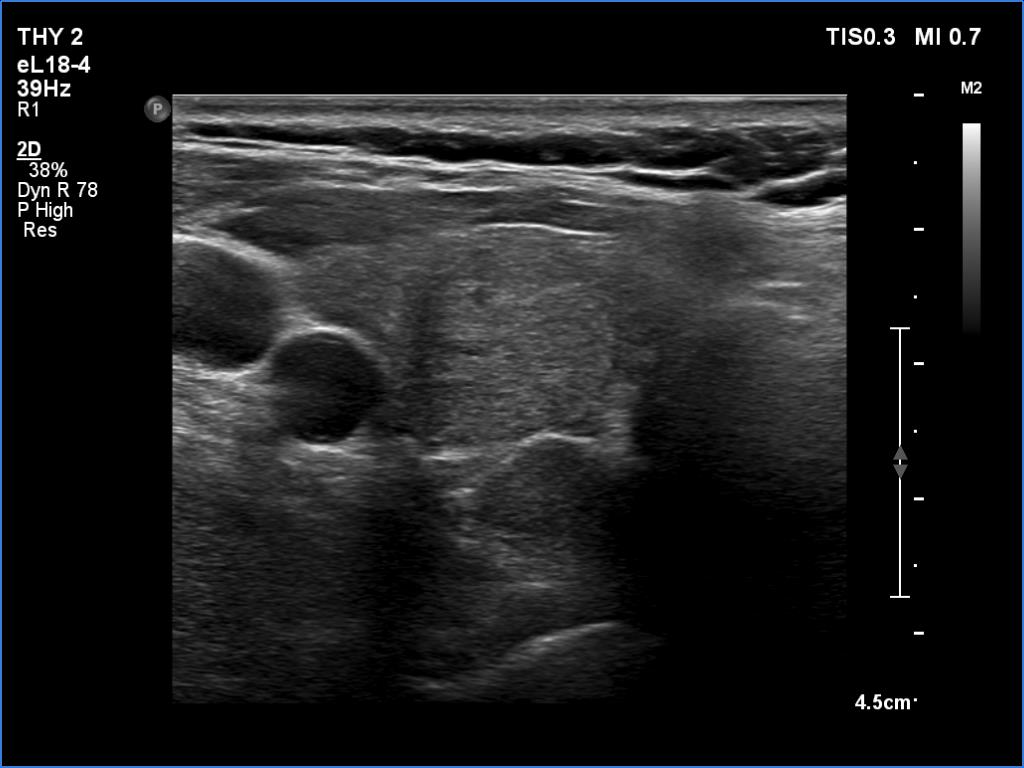

Clinical data: A 61-year-old woman was referred for preoperative localization of a parathyroid adenoma. The patient has been treated for hypothyroidism for seven years. Recently, hyperparathyroidism was diagnosed on evaluation of osteoporosis. MIBI scintigraphy disclosed increased uptake according to one of the left parathyroids.

Ultrasonography. The thyroid was moderately hypoechoic. There were two discrete lesions in the right lobe while a hypoechoic mass was found dorsal to the middle third of the left lobe.